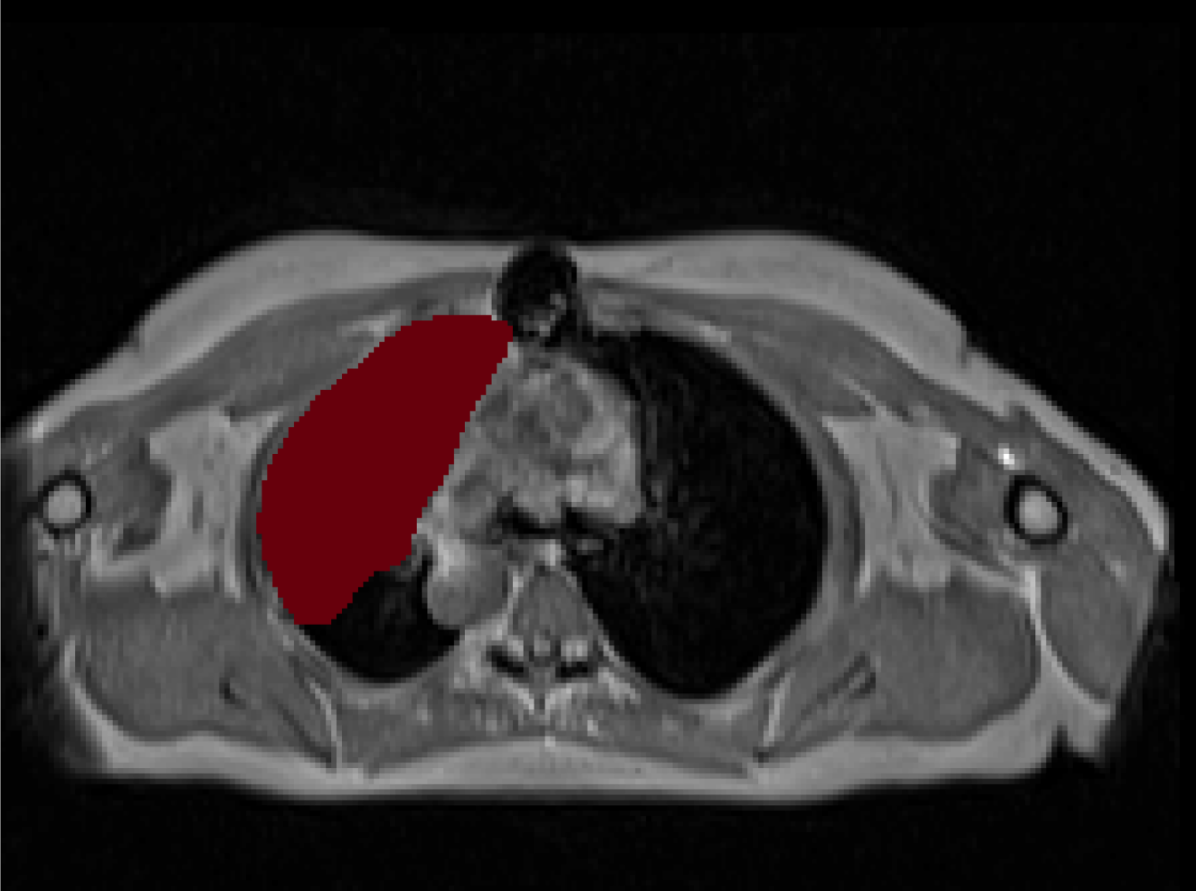

\captionof

figureUKBOB Size and Diversity. Our proposed UK Biobank Organs and Bones (UKBOB) is the largest labeled medical imaging dataset for segmentation, comprising body organs of 51,761 MRI 3D samples (17.9 M 2D images) and a total of more than 1.37 billion 2D masks of 72 organs. Left: we show label examples from UKBOB from axial, coronal, and sagittal views. Right: We show a plot of the size (number of 2D images) and diversity (number of classes) of our UKBOB compared to other medical images datasets. The size of the bubbles indicates 2D image resolution. This new scale in dataset size and diversity should unlock a new wave of applications and methods in the computer vision and medical imaging communities.